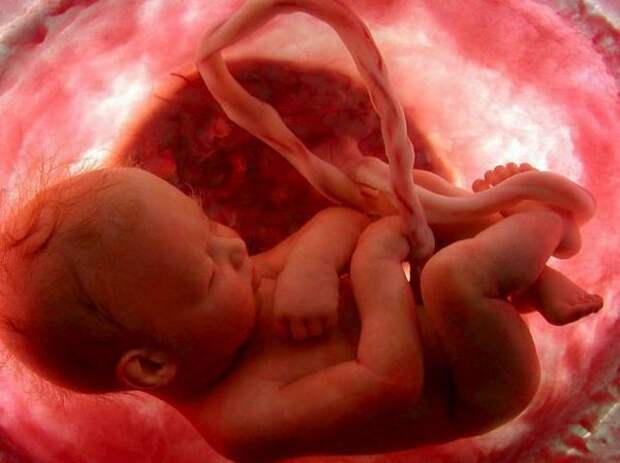

Этапы развития ребенка в утробе: фотографии и ультразвуковые снимки

Раздел: Лаборатория идей